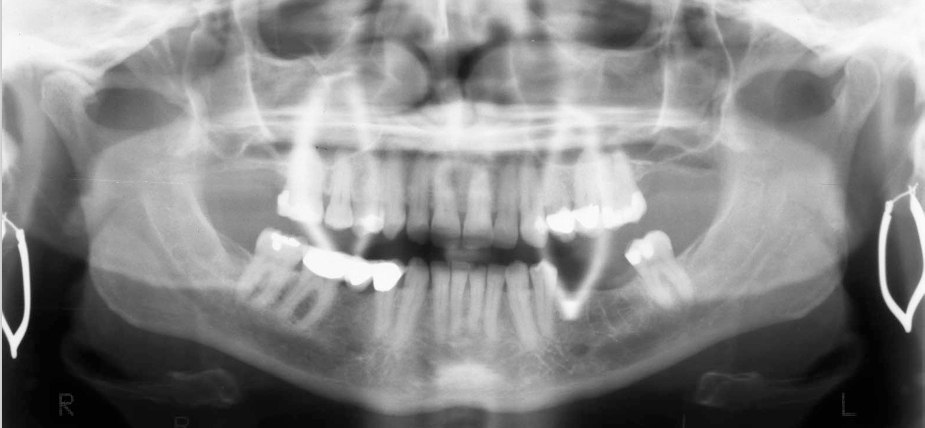

What should you be able to see with proper positioning for a panoramic?

A

• Teeth and jaws sharply depicted.

• Slight curvature of occlusal plane.

• Equal magnification on left and right side.

• No air space obstructing view of maxillary roots.

• No ghost image of cervical spine in midline